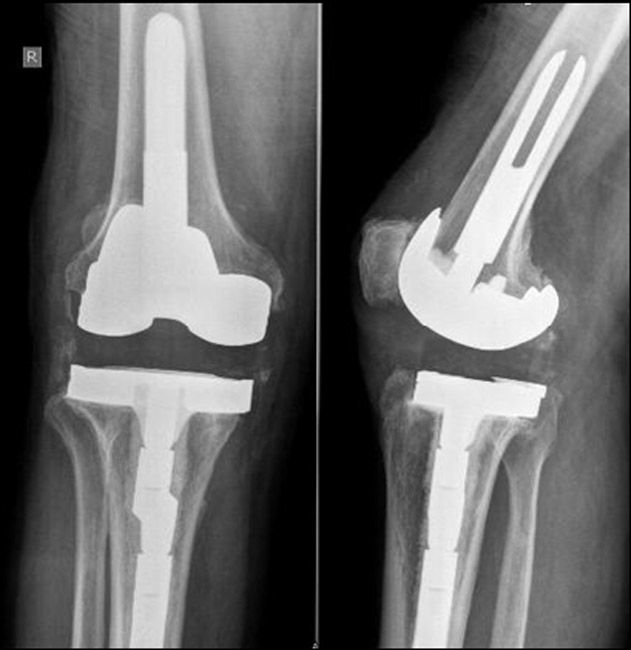

X-ray of knee replacement and antibiotic spacer

(Top) These X-rays show an original knee replacement from the front and from the side. (Bottom) An antibiotic spacer has been placed in the joint during the first stage of treatment for joint replacement infection.

Spacers are made with bone cement that is loaded with antibiotics. The antibiotics flow into the joint and surrounding tissues and, over time, help to eliminate the infection.

Patients who undergo staged surgery typically need at least 6 weeks of IV antibiotics, or possibly more, before a new artificial joint can be implanted.